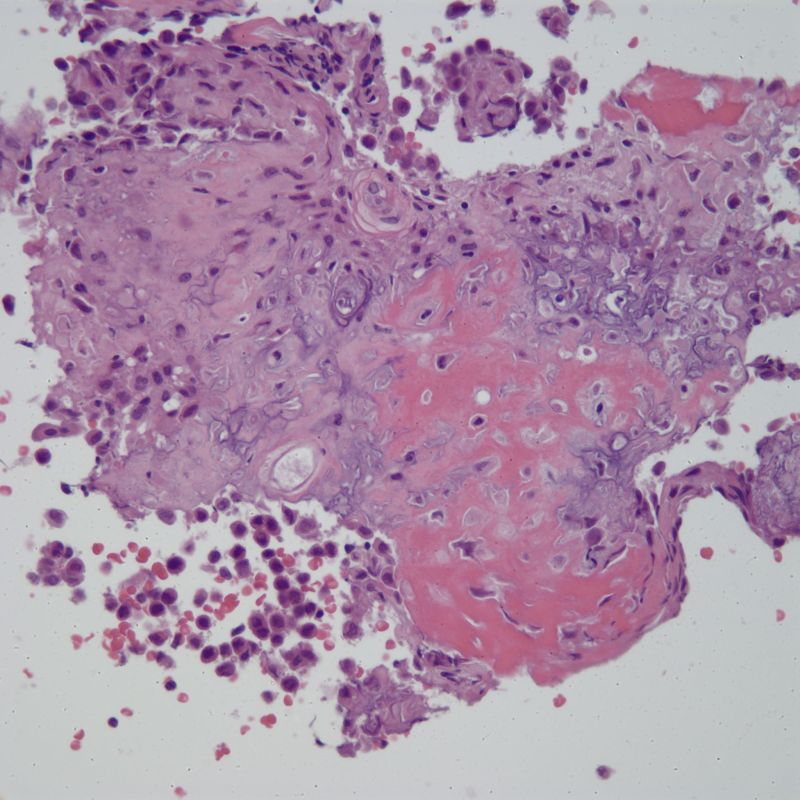

Chondroblastoma

- Diagnosing bone tumors can be challenging on limited biopsies.

- Small, crushed

- Note: “chicken-wire calcification” is not always present